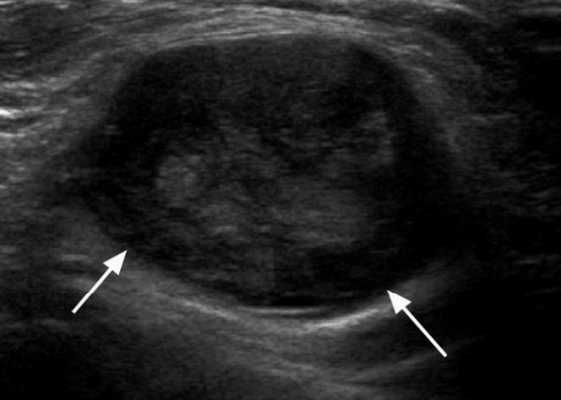

Практически во всех случаях дифференцировали лимфатический узел Кютнера (югулодигастральный), расположенный на границе средней и верхней трети шеи. Выявляемые лимфатические узлы имели размеры от 0,5 х 0,2 см до 2,3 х 0,8 см. УЗ-оценку производили после полипозиционного осмотра и нахождения самой длинной горизонтальной оси, что и принимали за максимальный поперечный диаметр. Большая часть лимфатических узлов (187) имели овальную форму с соотношением поперечного/переднезаднего более 1 (рис. 1 - 3). Тенденцию к округлению имели 30 лимфатических узлов, соотношение поперечного/переднезаднего приближалось к 1.

Рис. 1. УЗ-томограмма увеличенного реактивно измененного лимфатического узла: а - на фоне аденовирусной инфекции, б - после проведения противовоспалительного лечения

Мы установили, что, как правило, более округлая конфигурация лимфатического узла при его размерах, превышавших 10 мм, сопровождалась небольшими болевыми ощущениями, и более выраженной простудной (воспалительного характера) симптоматикой. Лимфатические узлы менее 10 мм чаще всего плохо пальпировались, либо вообще не выявлялись пальпаторно. Во всех случаях эхографически хорошо дифференцировался гипоэхогенный кортикальный слой и широкое, средней или чуть ниже средней эхогенности изображение области ворот лимфатических узлов. Четкость дифференциации составных частей лимфатического узла была снижена при размерах менее 5 мм. Мы отмечали различную толщину гипоэхогенного изображения области коры лимфатического узла: от очень широкой - при выраженности или прогрессировании воспалительного процесса, до узкой - на фоне положительной динамики.